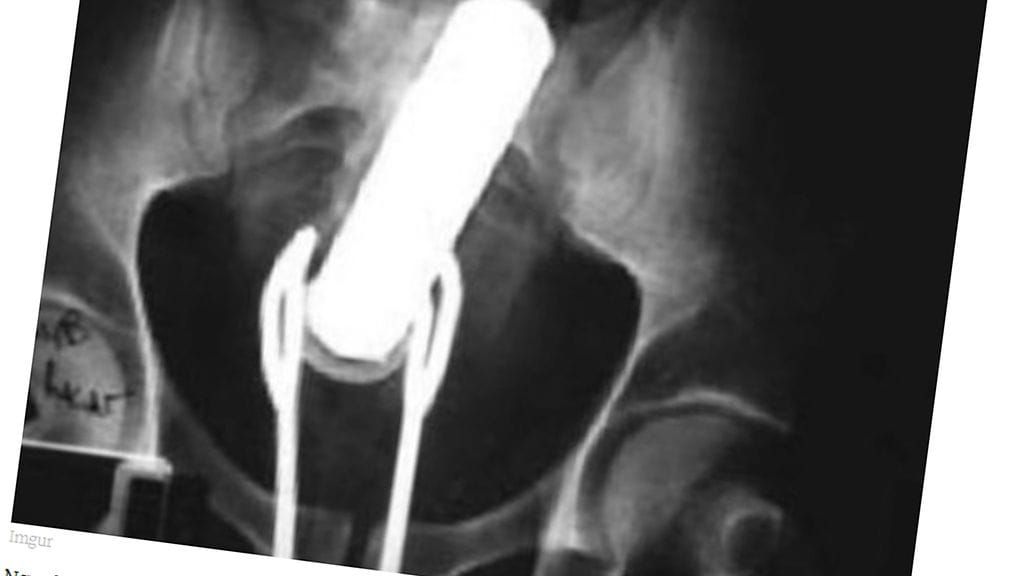

Erikoiset röntgenkuvat saavat ihmettelemään vain yhtä asiaa: voivatko ihmiset oikeasti olla näin typeriä?

Mikä menee sisään, ei välttämättä tule ulos ihan itsestään. Unilad-sivuston julkaisemat röntgen-kuvat asioista, joita himokkaat miehet ovat sisäänsä tunkeneet, eivät ensituntumalta vaikuta edes mahdollisilta.